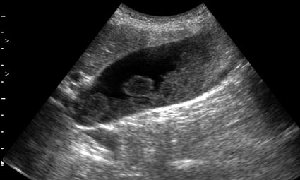

Женщина 59 лет с болями в подребрье справа.

- Сонограмма желчного пузыря при поступлении в стационар.